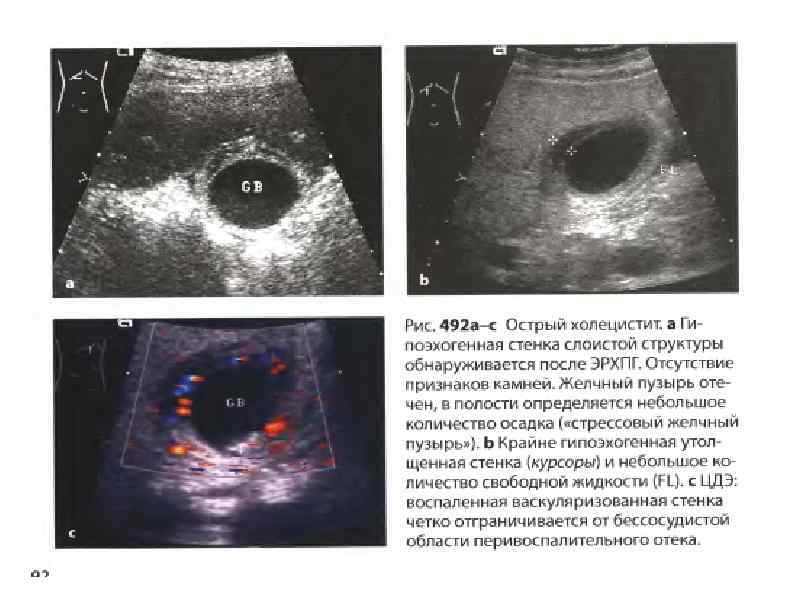

Сонографические признаки ОХЦ Сонографические признаки ОХЦ

Клинический случай: УЗИ — стенки ЖП утолщены (4 мм), выявлены свободно лежащие камни. Ультразвуковой Клинический случай: УЗИ — стенки ЖП утолщены (4 мм), выявлены свободно лежащие камни. Ультразвуковой симптом Murphy местное мышечное напряжение при давлении на переднюю брюшную стенку датчиком, расположенным непосредственно над дном желчного пузыря. Проверяется, если во время УЗИ выявлены желчные камни и утолщение стенки желчного пузыря.